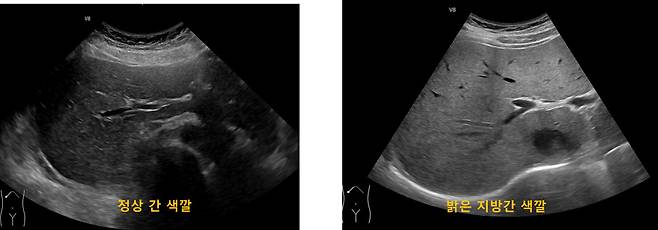

체중은 그대로인데 배만 서서히 나온다면, 이는 단순한 살이 아니라 지방간과 대사 이상의 신호일 수 있다.

간에 지방이 쌓이면, 전체 체중 변화 없이도 복부 중심으로 체형이 바뀐다. 특히 술을 많이 마시지 않아도 이런 변화가 나타난다면 더 주의가 필요하다. 간이 지방을 처리하지 못하고 있다는 뜻이기 때문이다.